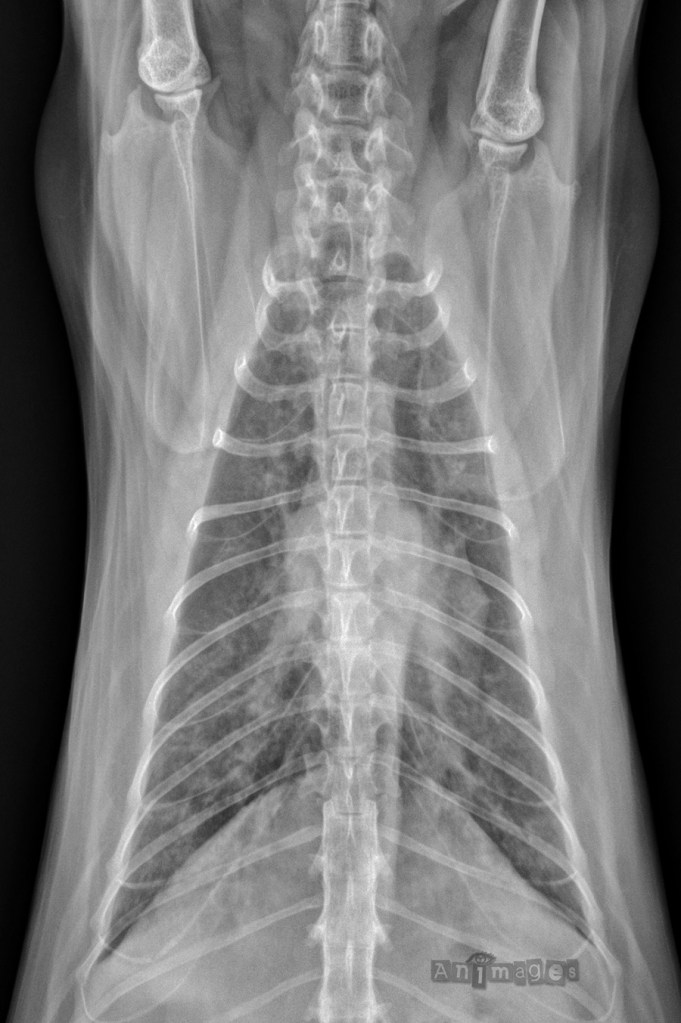

VD du thorax